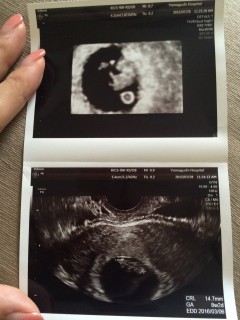

初診から16日後の8w2dでしたが、 2度計測したところ 大きさ的に7w5dCRL1.04と1.13cmと書かれていました。 やはり計測には誤差が出そうですね。 前回の我が子は心拍が確認するまではいけなかったのですが 無事心拍を確認出来て、元気ですね。と言っていただき もう嬉しくて嬉しくて。 早いはずなのに、もう目と鼻が見えてる気がしちゃいます。 次で数週が確定します!赤ちゃんがんばってね

二回目の検診。前回の豆粒みたいな写真から随分人間らしくなりました。卵黄嚢もバッチリ写っていて、栄養をきちんと取れているようでした。丁寧な先生で、様々な角度から撮って下さり、ベストショットを下さいました。